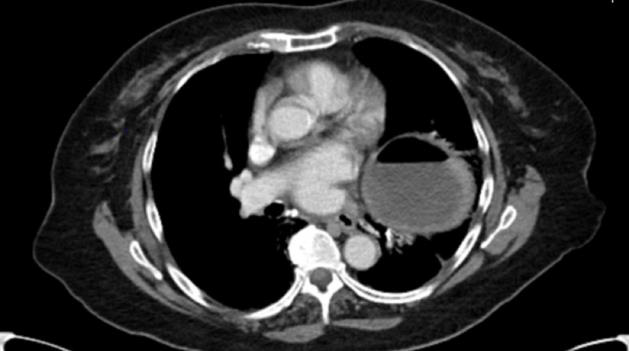

Exam was significant only for mild epigastric and left upper quadrant abdominal tenderness, with a soft, non-distended abdomen and normal bowel sounds. The patient’s vital signs remained stable throughout her ED stay. She was first given IV fluids, pantoprazole, and ondansetron for symptom control during the ED workup. The patient reported significant relief of pain after NG tube decompression. Pain control was continued with IV acetaminophen and morphine. Labs, including CBC with differential, CMP, lactic acid, and PT/PTT were significant for hypokalemia (3.2mmol/L) and mild hyperglycemia (108mg/dL). Other lab findings were within normal limits. An abdominal/pelvic CT with contrast revealed a diaphragmatic hernia with displacement of the gastric antrum and pylorus above the level of the GE junction and fundus extending into the left hemithorax through a diaphragmatic defect in a configuration compatible with a mesenteroaxial gastric volvulus and a probable associated gastric outlet obstruction. There was no bowel wall thickening or free perforation noted on CT. The case was then referred to a thoracic surgeon. The patient was transferred to a tertiary care center for surgical repair. The patient underwent an esophagogastroduodenoscopy, a laparoscopic paraoesophageal hernia repair with mesh, and Nissen fundoplication.

The most sensitive and specific diagnostic findings via radiology have been found to be the presence of both an antropyloric transition point without any abnormality at the transition zone and an abnormally located antrum at the same level or higher than the fundus [9]. Additional CT signs of gastric volvulus can include a transition point at the pylorus, a herniation of the antrum into the left hemithorax, an antropyloric junction above the gastroesophageal junction, a reversed position of the greater and lesser gastric curvatures, and stenosis of the gastric segments through the stretched oesophageal hiatus, clearly seen on the coronal reconstruction [9]. Contrast CT images can also show the direction and level of the volvulus, and the location of the transition point (the level of the volvulus) [10]. With a mesenteroaxial volvulus, as seen in this patient, CT will also show antral and distal body herniation into the left hemithorax with an inferiorly located esophagogastric junction below the diaphragm [11].